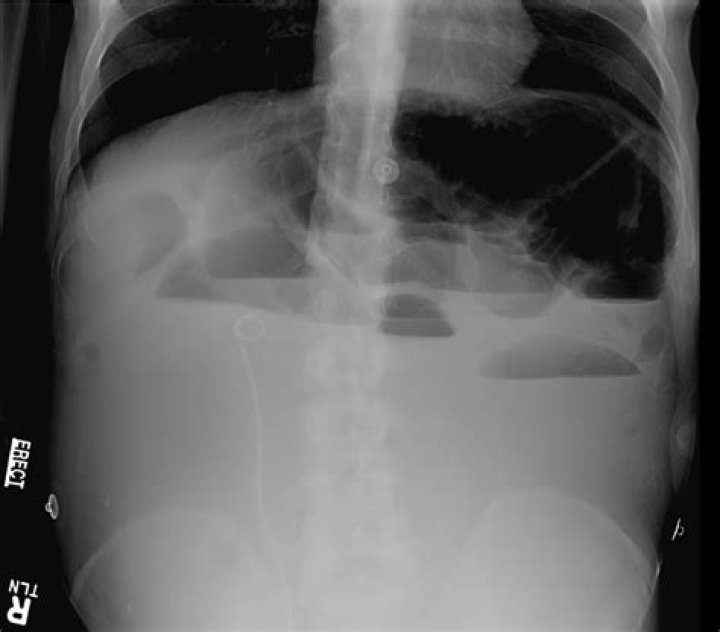

A kidney, ureter, and bladder (KUB) X-ray is also known as a “flat plate of the abdomen x-ray,” may be performed to assess the abdominal area for causes of abdominal pain, or to assess the organs and structures of the urinary and/or gastrointestinal (GI) system.

: a radiograph especially of the abdomen taken with the subject lying flat.

To confirm a diagnosis of intestinal obstruction, your doctor may recommend an abdominal X-ray. However, some intestinal obstructions can’t be seen using standard X-rays. Computerized tomography (CT). A CT scan combines a series of X-ray images taken from different angles to produce cross-sectional images.